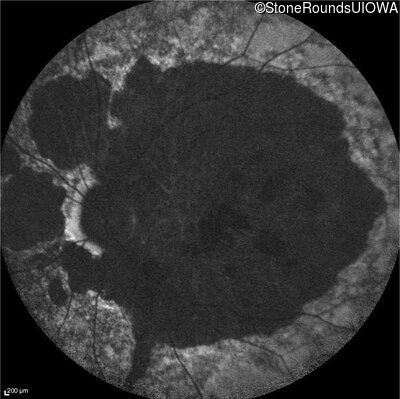

Infrared Fundus Photograph - Right - 20/200 sc

Exemplar